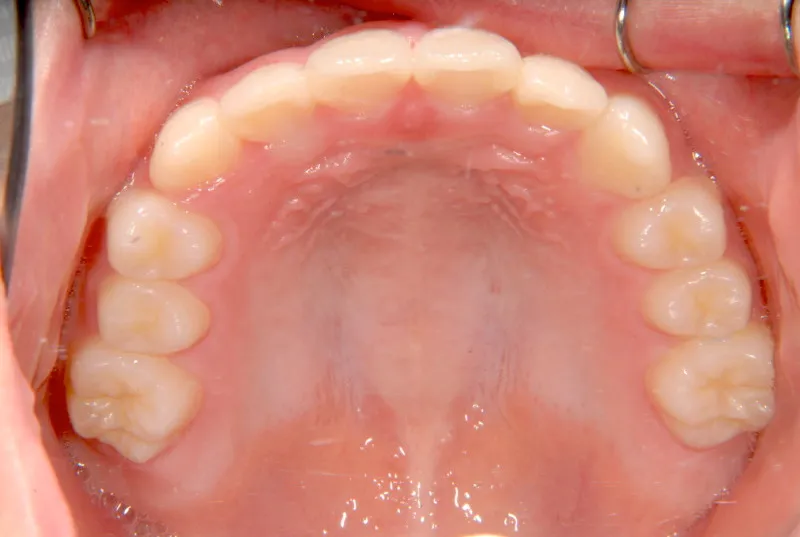

治療終了後

オリジナルの着け外しのできる装置で治療しました。

治療回数○回、4年7ヶ月の治療期間で矯正治療を終了しました。

1期治療で十分な結果が得られたと思います。